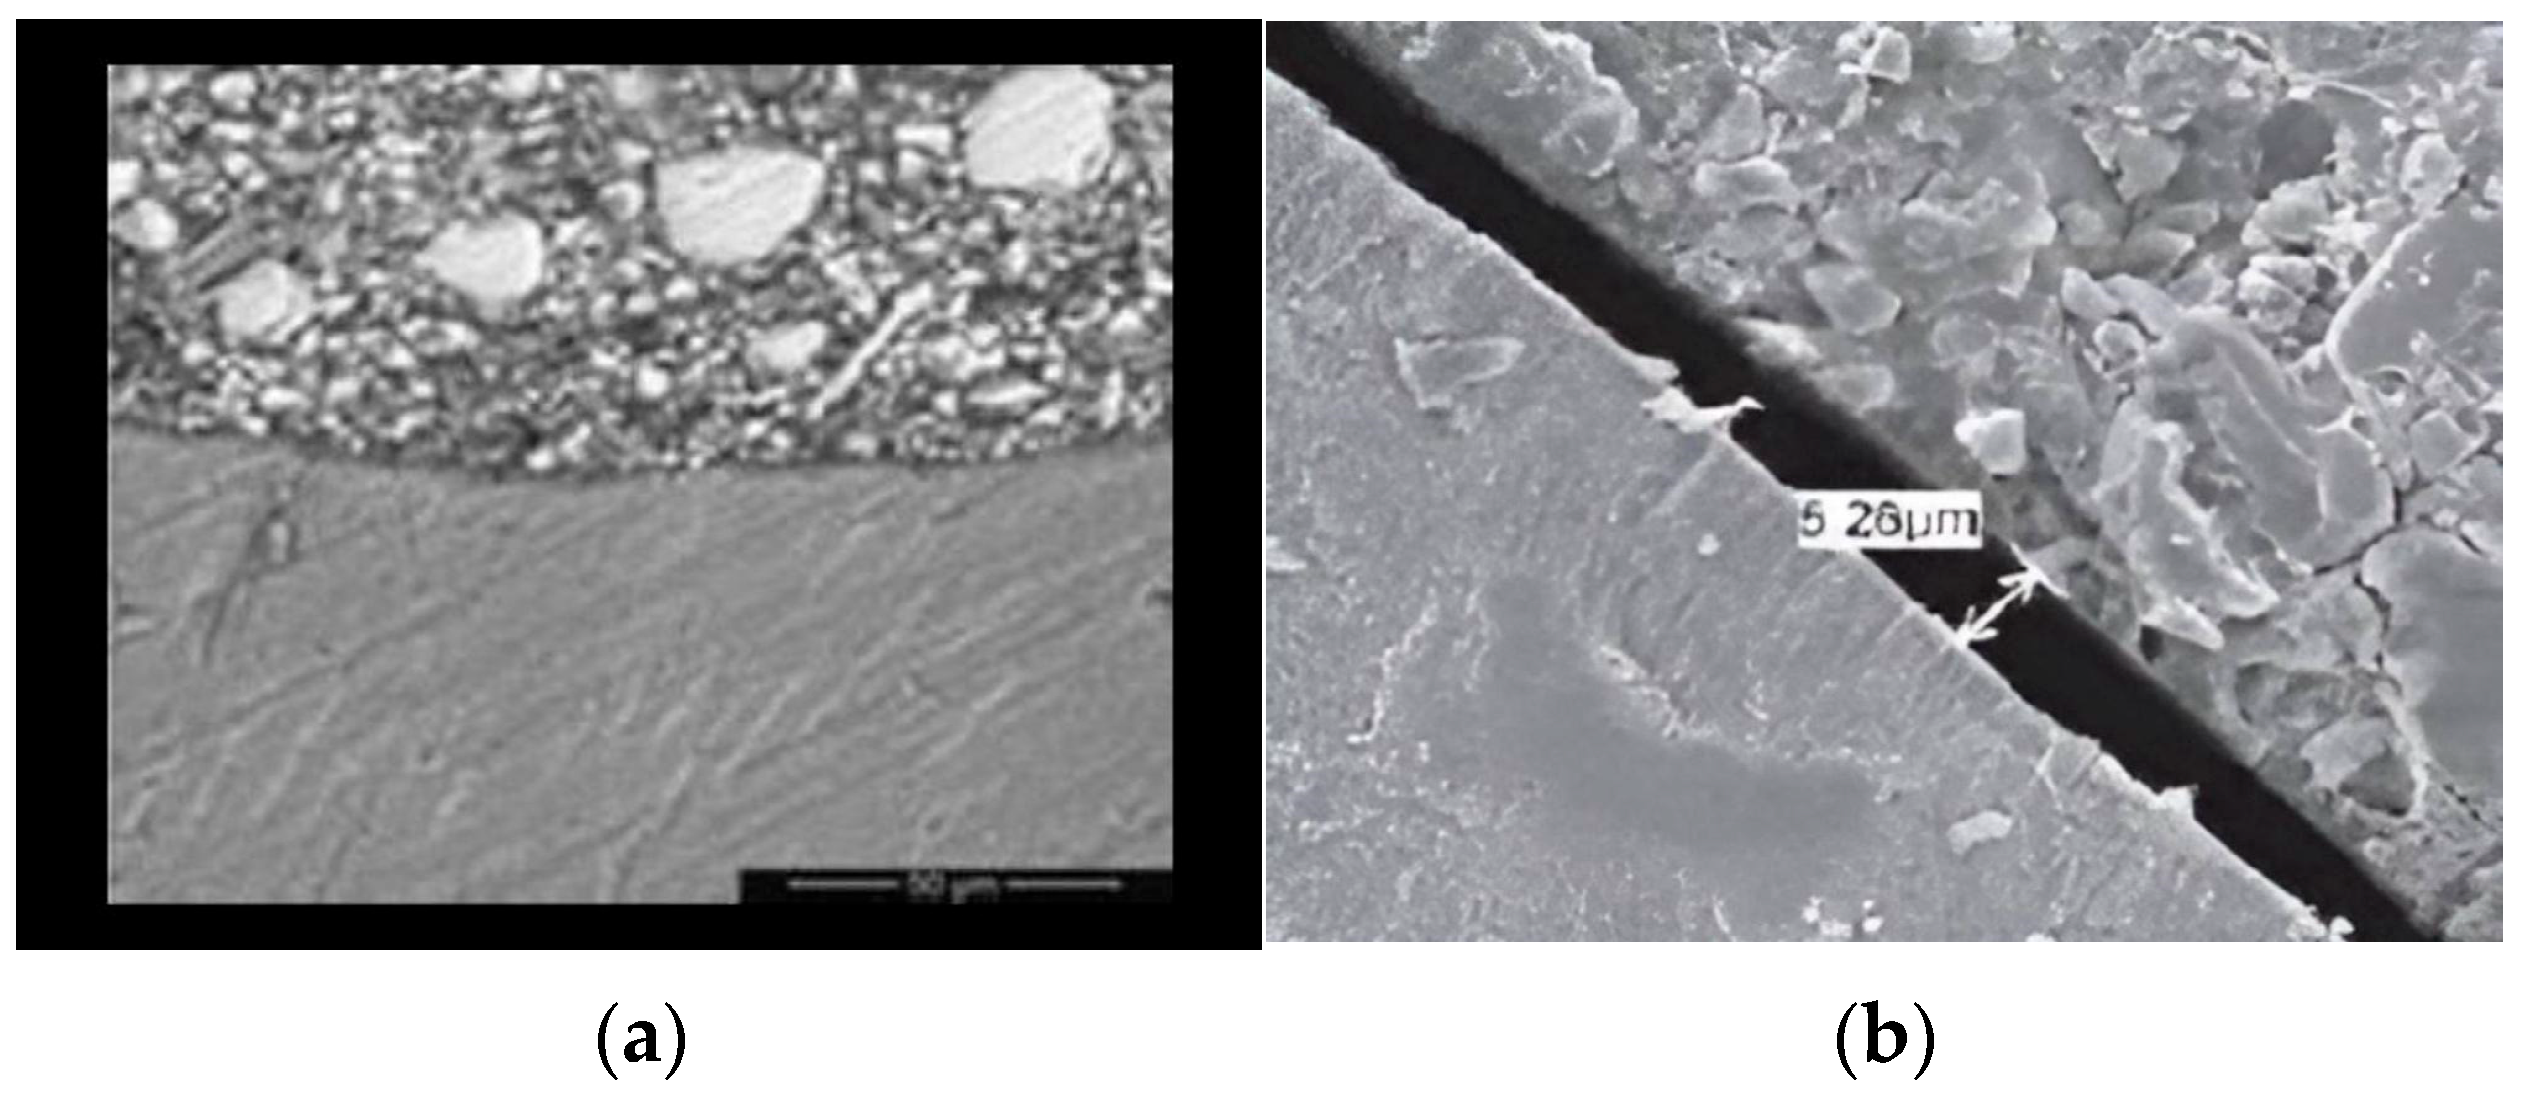

2.3. SEM Specimen Preparation and Evaluation

- Samy, F.M.; El-Kholany, N.R.; Hamama, H.H. Micromorphological Analysis of Different Bioactive Restorative Materials/Dentin interface: A Comparative In Vitro Study. Egypt. Dent. J. 2024, 70, 3909–3916. [Google Scholar] [CrossRef]